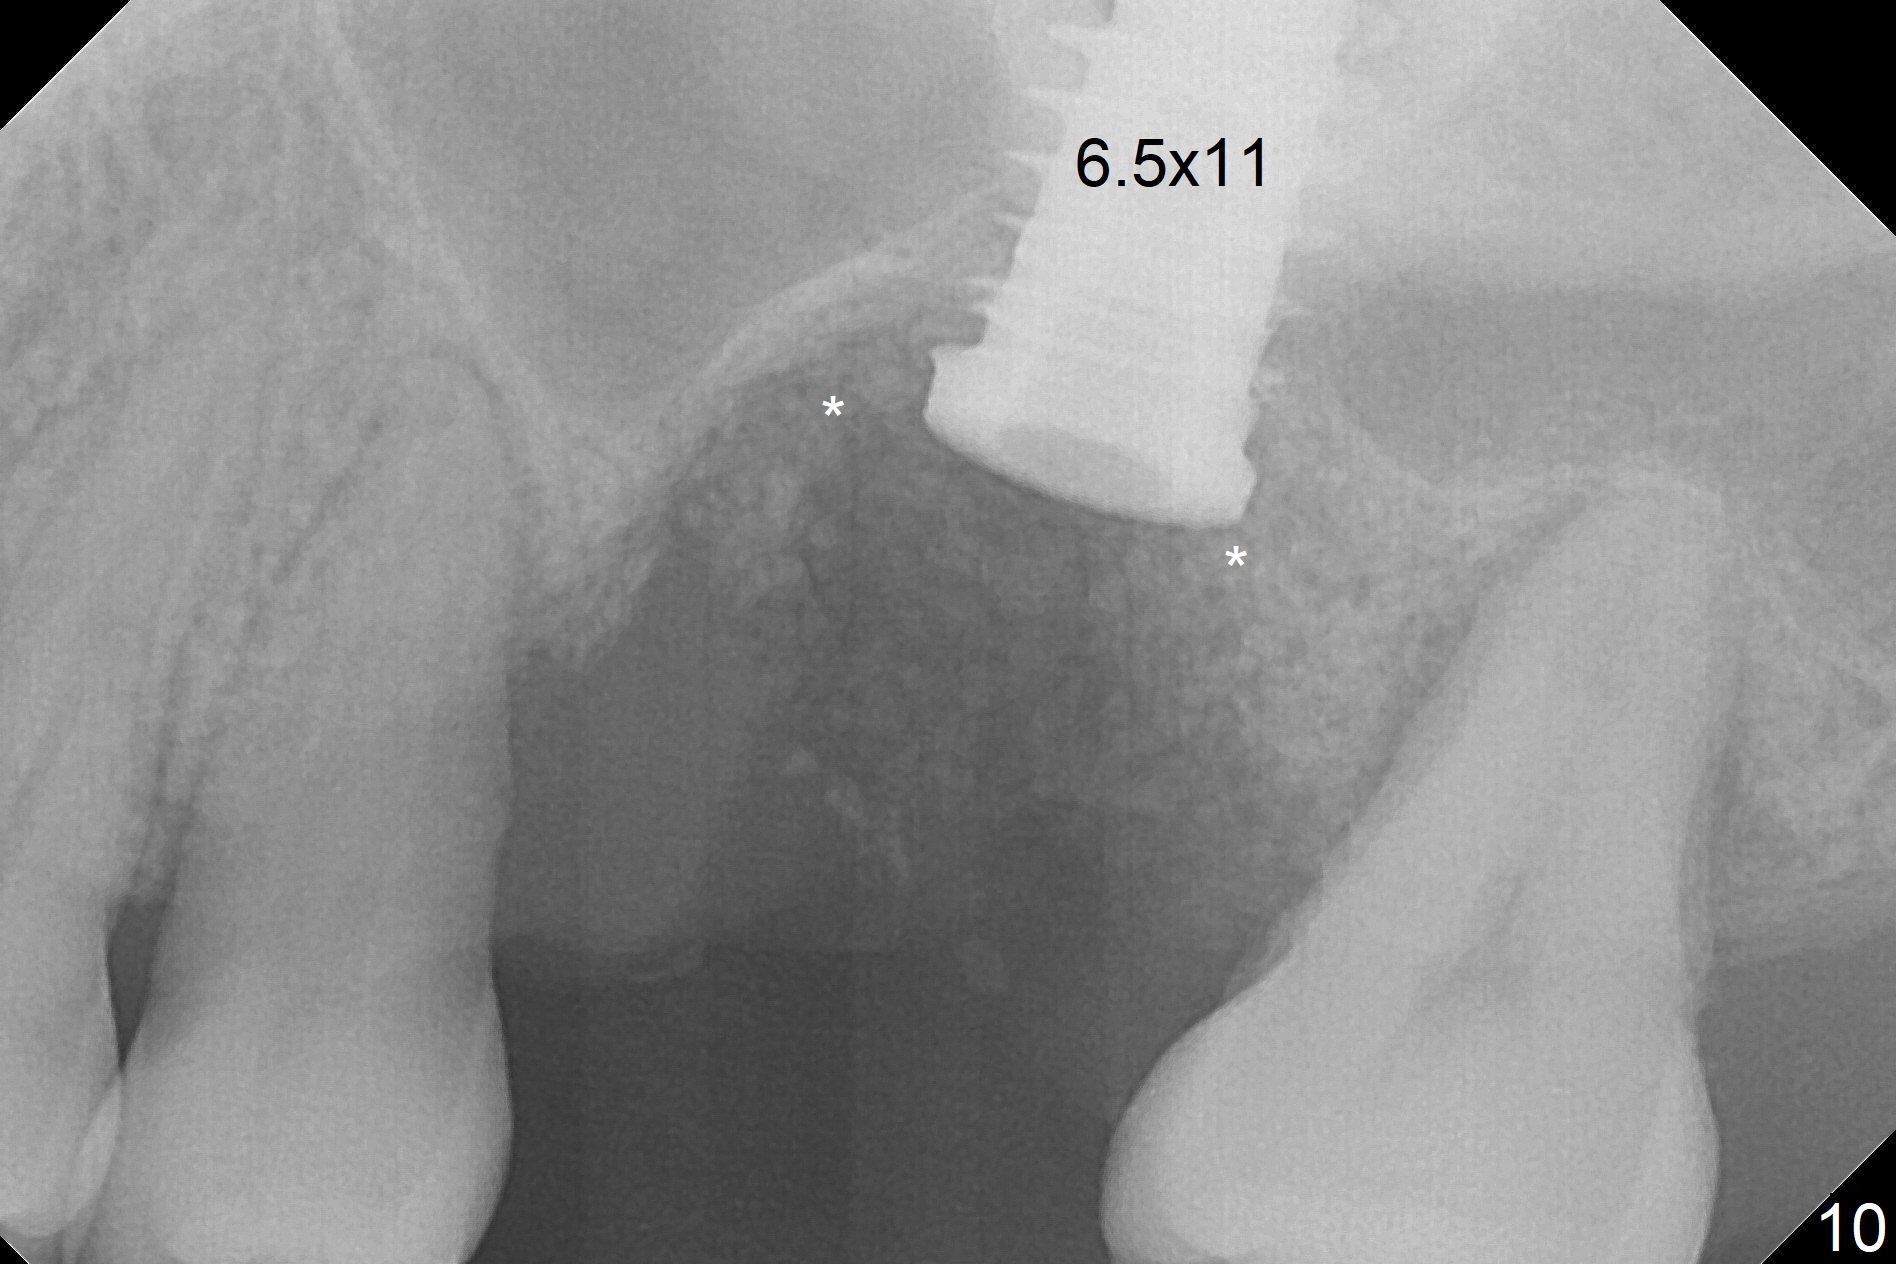

When the displaced tooth #14 (Fig.1) with palatal gingival recession (Fig.2) is extracted, the buccal plate is low, while the palatal one is lost.  Osteotomy is initiated in the bottom of the large socket with Marking Drill.  The bone turns bluish, suggesting thin bone (in fact less than 1 mm as well as low density).  Magic Sinus Lifter (Fig.3 *, Fig.4 blue area) is used for sinus lift (Fig.4 (red curved line: lifted sinus membrane; grey area: a portion of the lifted sinus floor), followed by insertion of a piece of PRF plug and Vanilla bone graft for sinus lift.  The osteotomy is enlarged lightly with 4.8 mm Magic Drill (compare black strips between Fig.4,5).  A 5x9 mm dummy implant (Fig.5 green) is dislodged into the sinus.  The lifted sinus membrane holds the implant in place.  The black thin strip in Fig.5 and black circle in Fig.6a (occlusal view) represents the osteotomy.  After increase in the osteotomy with Lindamann bur (Fig.6b red circle), the implant (Fig.6c green) is retrieved with endodontic forceps (Fig.6c two blue dots (beaks of the forceps); Fig.7,8).  With the enlarged osteotomy (Fig.6d), a 6x9 mm dummy implant is placed deep (Fig.9).  The definitive implant is 6.5x11 mm with insertion torque ~ 15 Ncm (Fig.10).  With placement of a healing screw and further placement of allograft (Fig.11 *), the socket is closed with PRF membrane and collagen plug (Fig.12).

Questions for Dr. Wang: Can we remove the coronal portion of the bone (Fig.13) and back up the implant (Fig.14 arrow) 4-5 months postop for easy restoration?  If it is not a good option, can we produce pair abutments with 5 and 7 mm cuffs?

Poor visibility for immediate implant in the molar region is another contributing factor for the dislodgement.  The patient returns for follow up 15 days (Fig.15) and 1 month (Fig.16) postop.  Bone graft seems to be stable around the implant.  The socket heals 4 months postop (Fig.20).  The implant seems to have been osteointegrated (Fig.17,18).  It will be backed up for ~ 3 mm to improve implant/crown ratio (Fig.19, as compared to Fig.14).  If it cannot be done, take impression immediately and make a subgingival provisional before suturing.

In fact, there is no coronal bone for the implant to be backed up.  Therefore, impression is taken after uncover and insertion of a 5.5x5.7(4) mm abutment.